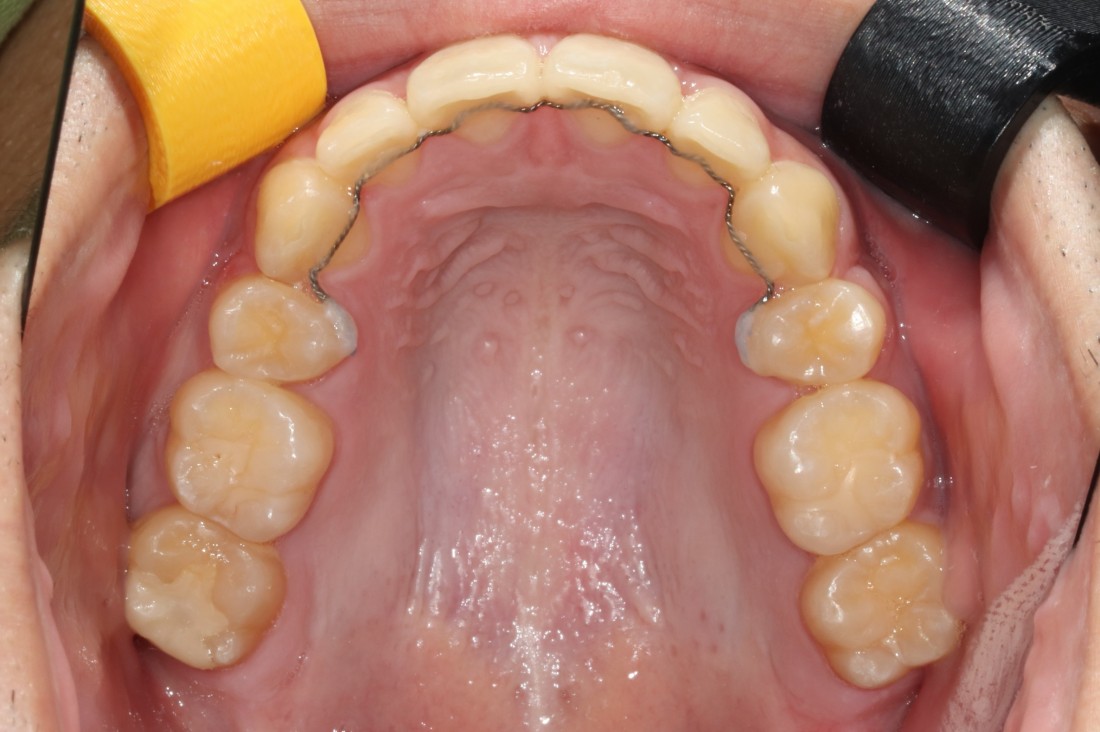

광주 개방교합 교정을 위해

방문해주신 30대 남성 환자분의

교정 전 사진입니다.

어금니를 맞닿게 하여서 입을 다물어도

윗니와 아랫니가 만나지 않는데요.